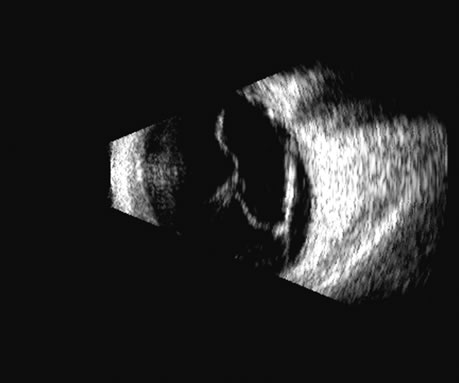

Fig. 16. 3D depiction of a retinal detachment can be helpful in situations in which there is ambiguity among retina, choroid, and schisis. The 3D rotatable display can be perceived from different perspectives, often aiding in the certainty of diagnosis.

The representation of volume and three-dimensional perspectives of the diseased vitreous, retinal detachment, choroidal detachment, and tumors can add to presurgical conceptualization and is critical to characterization of tumors in relation to prediction of lethality.45 In addition, volume measurement of the choroid permits studies of both surgical and physiologic rates of clearance of hemorrhage, whereas vitreous volume studies can make the estimation of gas or other vitreous substitutes for replacement more accurate (Fig. 25).